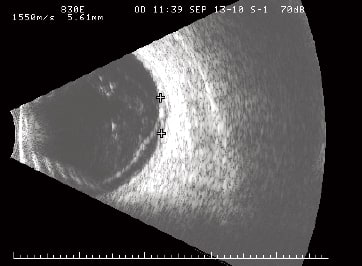

Since the patient's melanoma had an excellent response to brachytherapy that was documented over a 4-year period, we were able to consider surgical repair of the complex retinal detachment to restore the ocular anatomy and vision. Because the cataract was contributing to visual acuity loss and would confound the posterior segment repair, we elected to perform a single combined procedure. After we confirmed the tumor was involuted and saw no evidence of active melanoma on exam, imaging or ultrasound, we scheduled surgery.

Figures 1 and 1a. Malignant posterior uveal melanoma of the left eye in a 75-year-old Hispanic female.

Figure 2. Eighteen months after successful brachytherapy, the patient's left eye developed radiation retinopathy, which was treated over the course of 24 months with intravitreal bevacizumab. Vision stabilized at 20/50; however, a complex and progressive hemorrhagic retinal detachment developed.